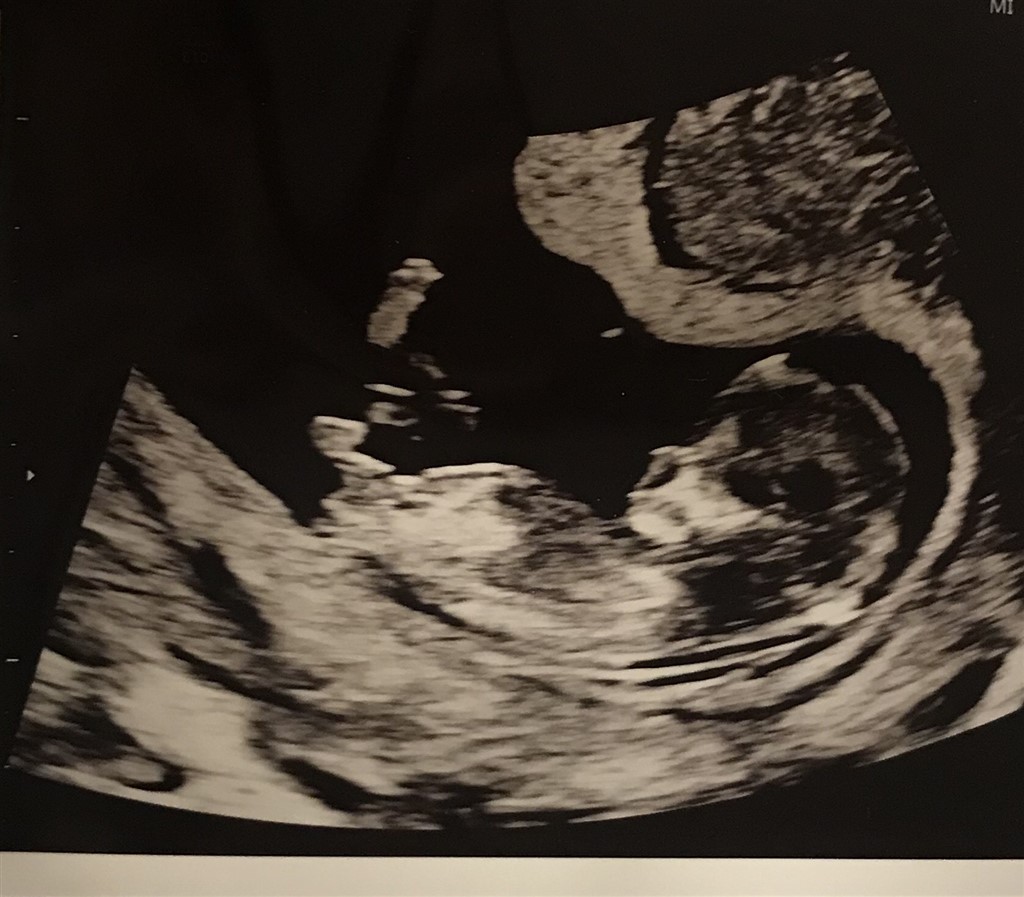

jeg vil høre, om nogen kunne tænke sig at komme med et bud på hvad køn i tror baby er? Enten ved at svare i afstemningen eller gerne ved at skrive en kommentar. Håber der er nogen derude som tør komme med et bud Er i uge 12+3 ��

Det er ikk så gode billeder til nub teorien synes jeg. Men umiddelbart er mit bud en pige

Uden tvivl pige ☺️

En pige!!